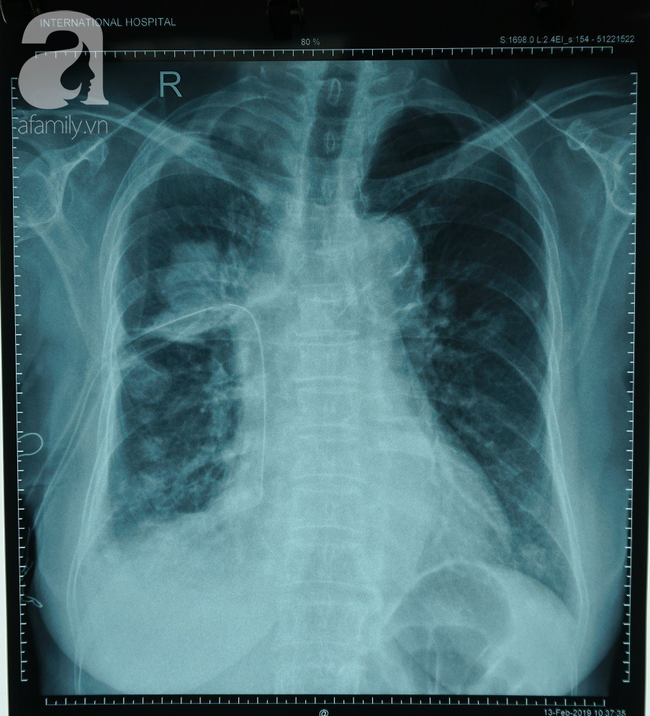

BS Lê Nguyễn Khánh Duy cho biết, ung thư phổi là ung thư hay gặp nhất trên toàn cầu, khó phát hiện sớm, kết quả điều trị cũng rất thấp, gây tử vong nhiều nhất trong các loại ung thư.

Bệnh có xu hướng di căn ngay cả trước khi có thể được phát hiện trên phim X-quang.

Có 2 loại chính của ung thư phổi là Ung thư phổi tế bào nhỏ (chiếm 10%, khi phát hiện đã cho xâm lấn và di căn xa) và Ung thư phổi không tế bào nhỏ (chiếm 90%, phát triển qua từng giai đoạn).

92% bệnh nhân ung thư phổi không tế bào nhỏ có thể sống trên 5 năm nếu phát hiện và điều trị ở giai đoạn sớm, khối u ung thư kích thước dưới 1 cm. Nếu đã di căn xa đến gan hoặc tuyến thượng thận thì tỉ lệ này là vô cùng thấp.